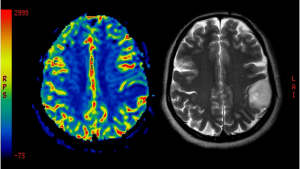

Die Diagnose der Lewy-Körperchen-Demenz kann eine Herausforderung darstellen, da sie aufgrund ihrer Ähnlichkeit zu anderen Erkrankungen wie Alzheimer und Parkinson oft fehldiagnostiziert wird. Ärzte stützen sich auf klinische Beobachtungen, bildgebende Verfahren und neuropsychologische Tests, um die richtige Diagnose zu stellen.